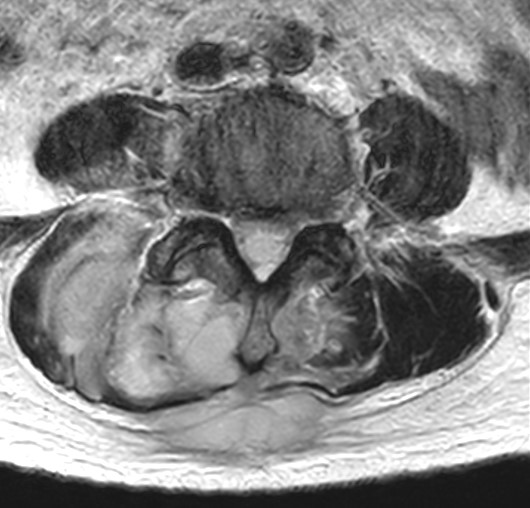

Rozsáhlý absces paravertebrálních svalů páteře zasahující do páteřního kanálu v bederní oblasti.

MRI s/ bez kontrastu je zlatým standardem – ukáže zánět, otok v okolí páteřního kanálu, abscesy a rozlišuje je od jiných onemocnění. RTG může ukázat zúžení disku nebo eroze kostí, ale jen v pozdějších stádiích (2+ týdny); CT je užitečné v pozdějších stadiích pro detekci kostních změn, kontrolu deformit nebo plánování biopsie.